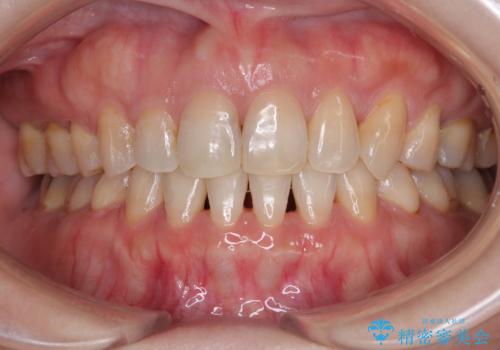

矯正歯科治療 → 上下顎前突(口ゴボ)

- デコボコと口元の突出感を改善 抜歯矯正治療